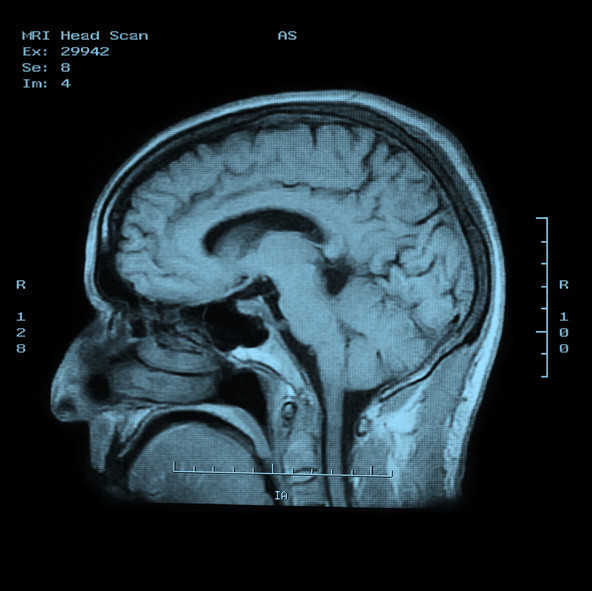

Flores’e, omurgasında gelişimsel bir kemik tümörü olan kordoma teşhisi kondu. Bu tümör türü ABD’de yılda yaklaşık 300 kişide görülüyor. Flores, 18 yaşında çift görme yaşamaya başladı ve aylar süren muayene ve tetkiklerin ardından nadir görülen bu teşhisle karşı karşıya kaldı. Tümör, kafatasının tabanından boyun omurlarına kadar yayılmıştı ve beyin sapını sarmıştı.

Ameliyatın riskleri oldukça yüksekti. Tümör, beyin sapı, omurilik ve ana kan damarlarına yakın konumdaydı. Dr. Labib, “Küçük bir hata felce ya da ölüme yol açabilirdi. Ancak ameliyat olmadan bu tümör büyümeye devam edecek, sinir sistemine baskı yapacak ve kaçınılmaz sonla sonuçlanacaktı” dedi.